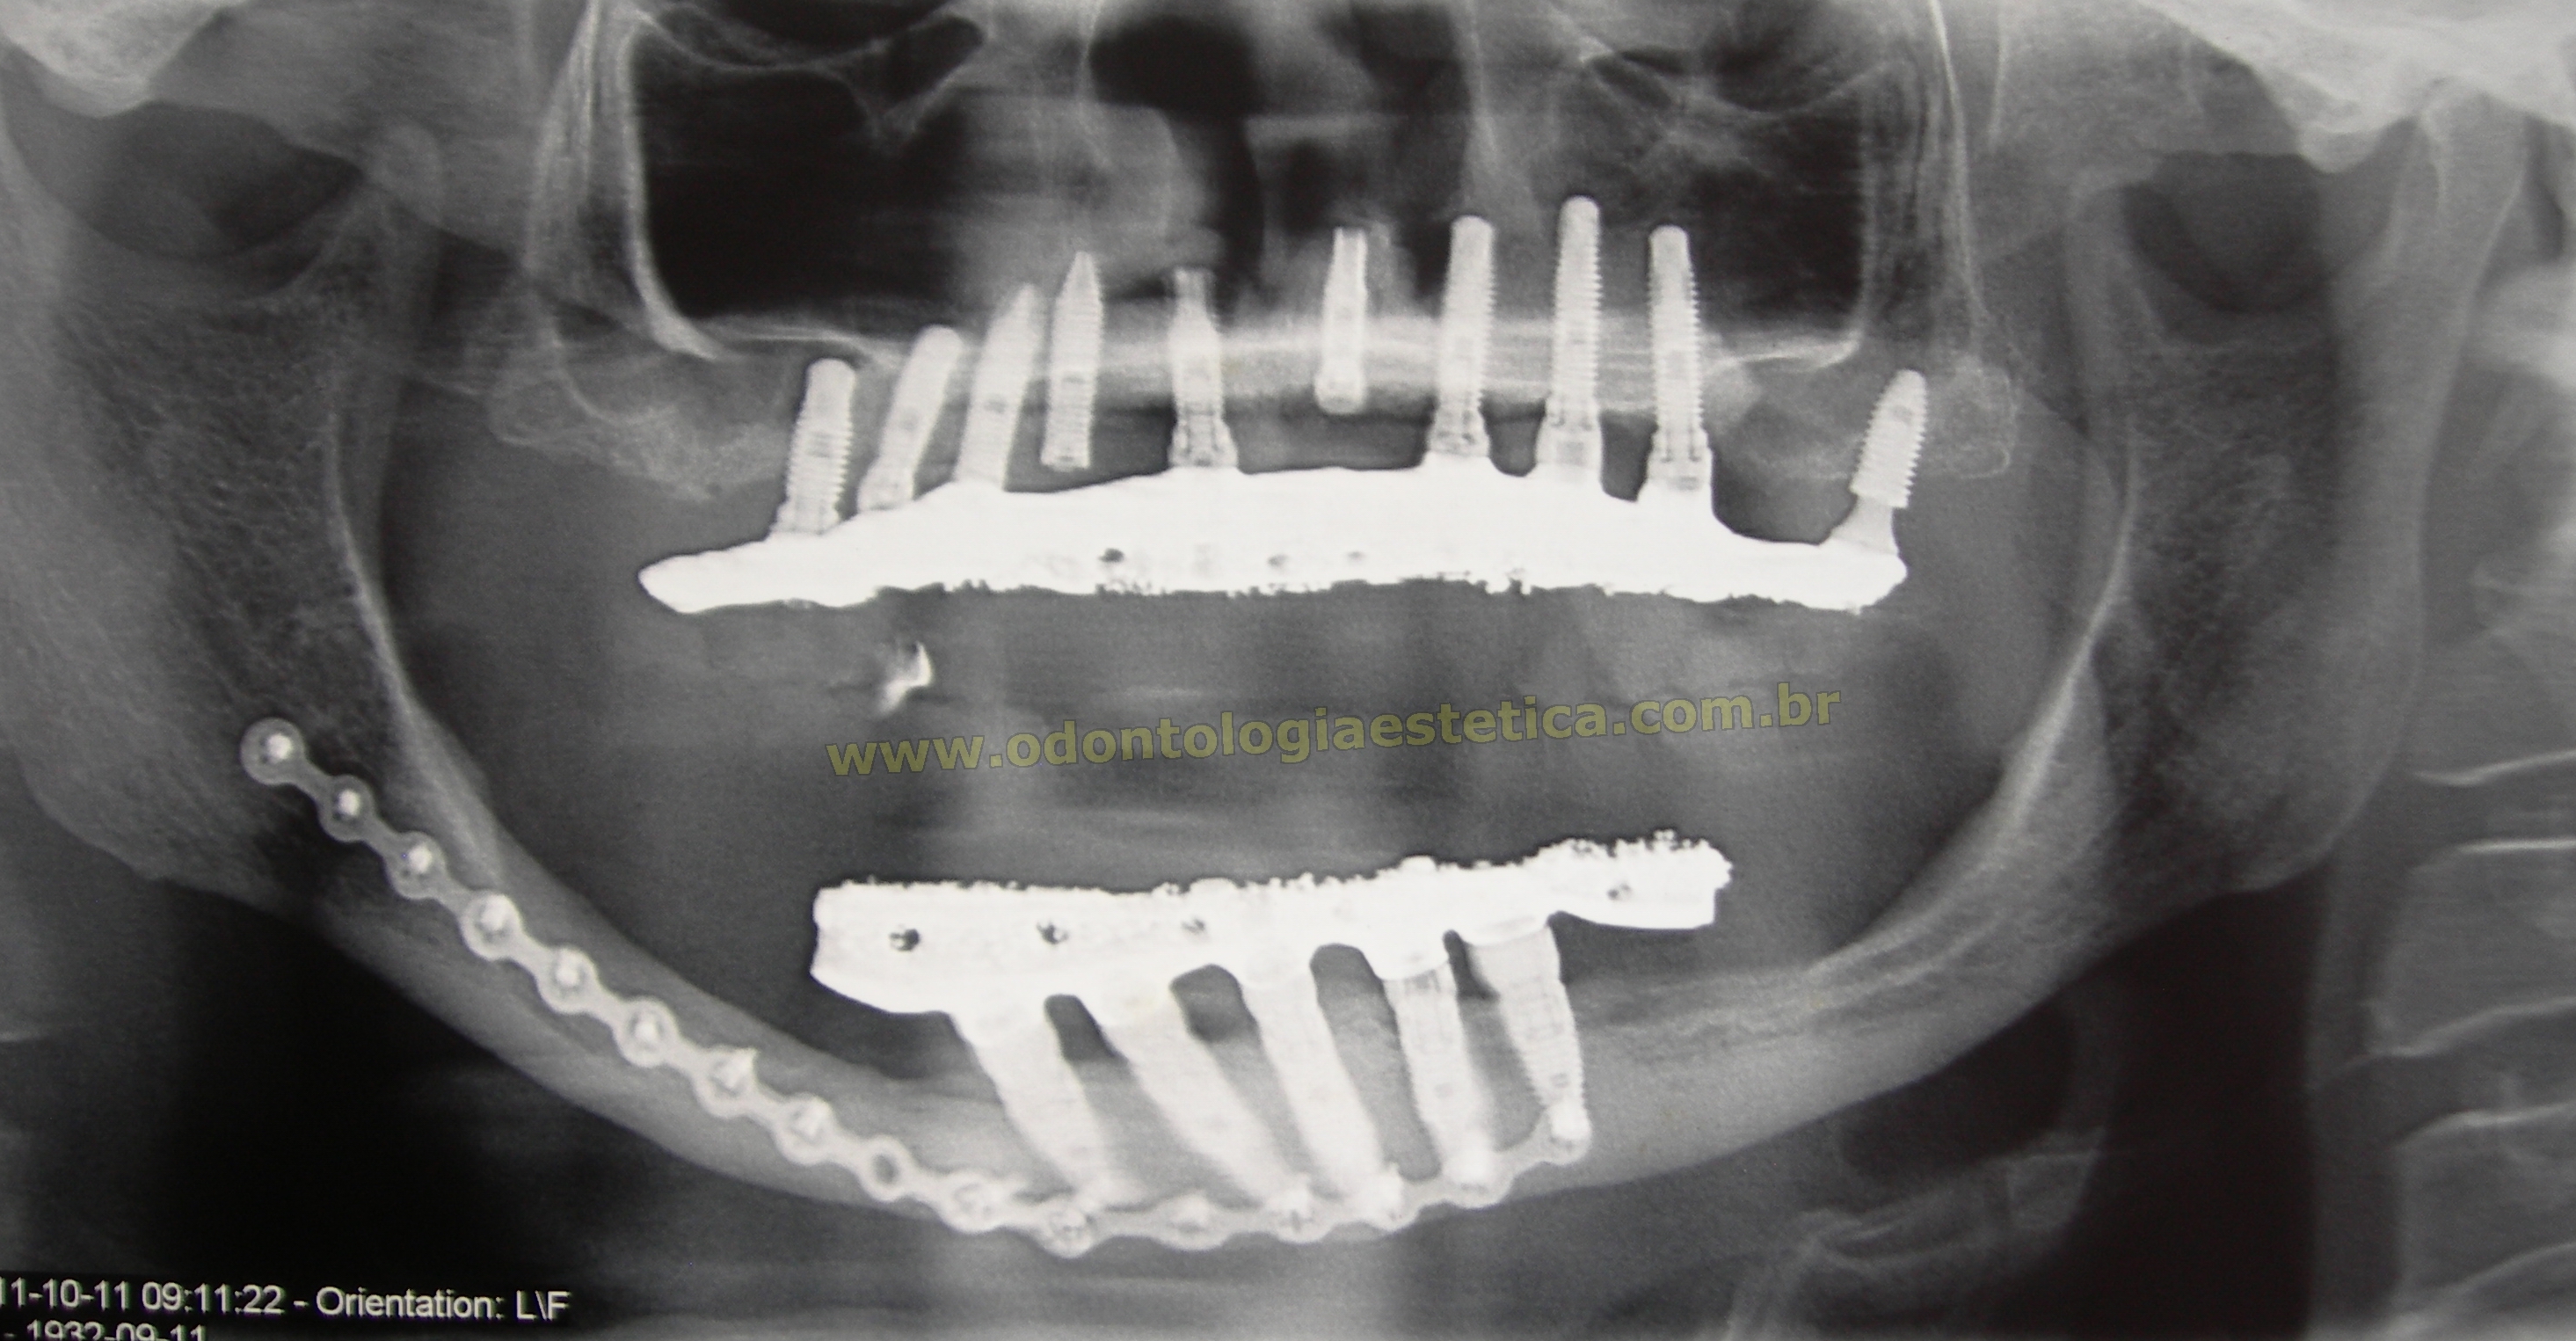

Tratamento  reabilitador combinado de maxila e mandíbula com implantes osseointegráveis sobre bases ósseas antes severamente atróficas e reconstruídas por enxertia óssea autógena de calota craniana, em paciente do sexo feminino, com idade relativamente avançada para um procedimento desse porte, vindo atestar que, cada vez mais a ciência e a prática clínica caminham juntas no intento de proporcionar melhoria na qualidade de vida dos pacientes acometidos por essas patologias.

A arcada superior recebeu um número elevado de implantes como prevenção à  possibilidade de perda de alguns elementos caso o padrão de reabsorção dos  enxertos excedesse ao esperado. Entretanto, nenhum dos elementos foi perdido; permitindo-nos assim, selecionar os apoios em áreas estrategicamente mais importantes. Admite-se, inclusive, dos 10 implantes, utilizar apenas 6 ou 7 para suporte de uma prótese nessas mesmas condições para a maxila.

implantes sobre  enxerto de calota occipital rx panoramico raio x panoramica radiografia panorâmica após enxerto reforço metálico por placas e implantes após tratamento reabilitadpor implantes em maxila e mandíbla severame atróficas